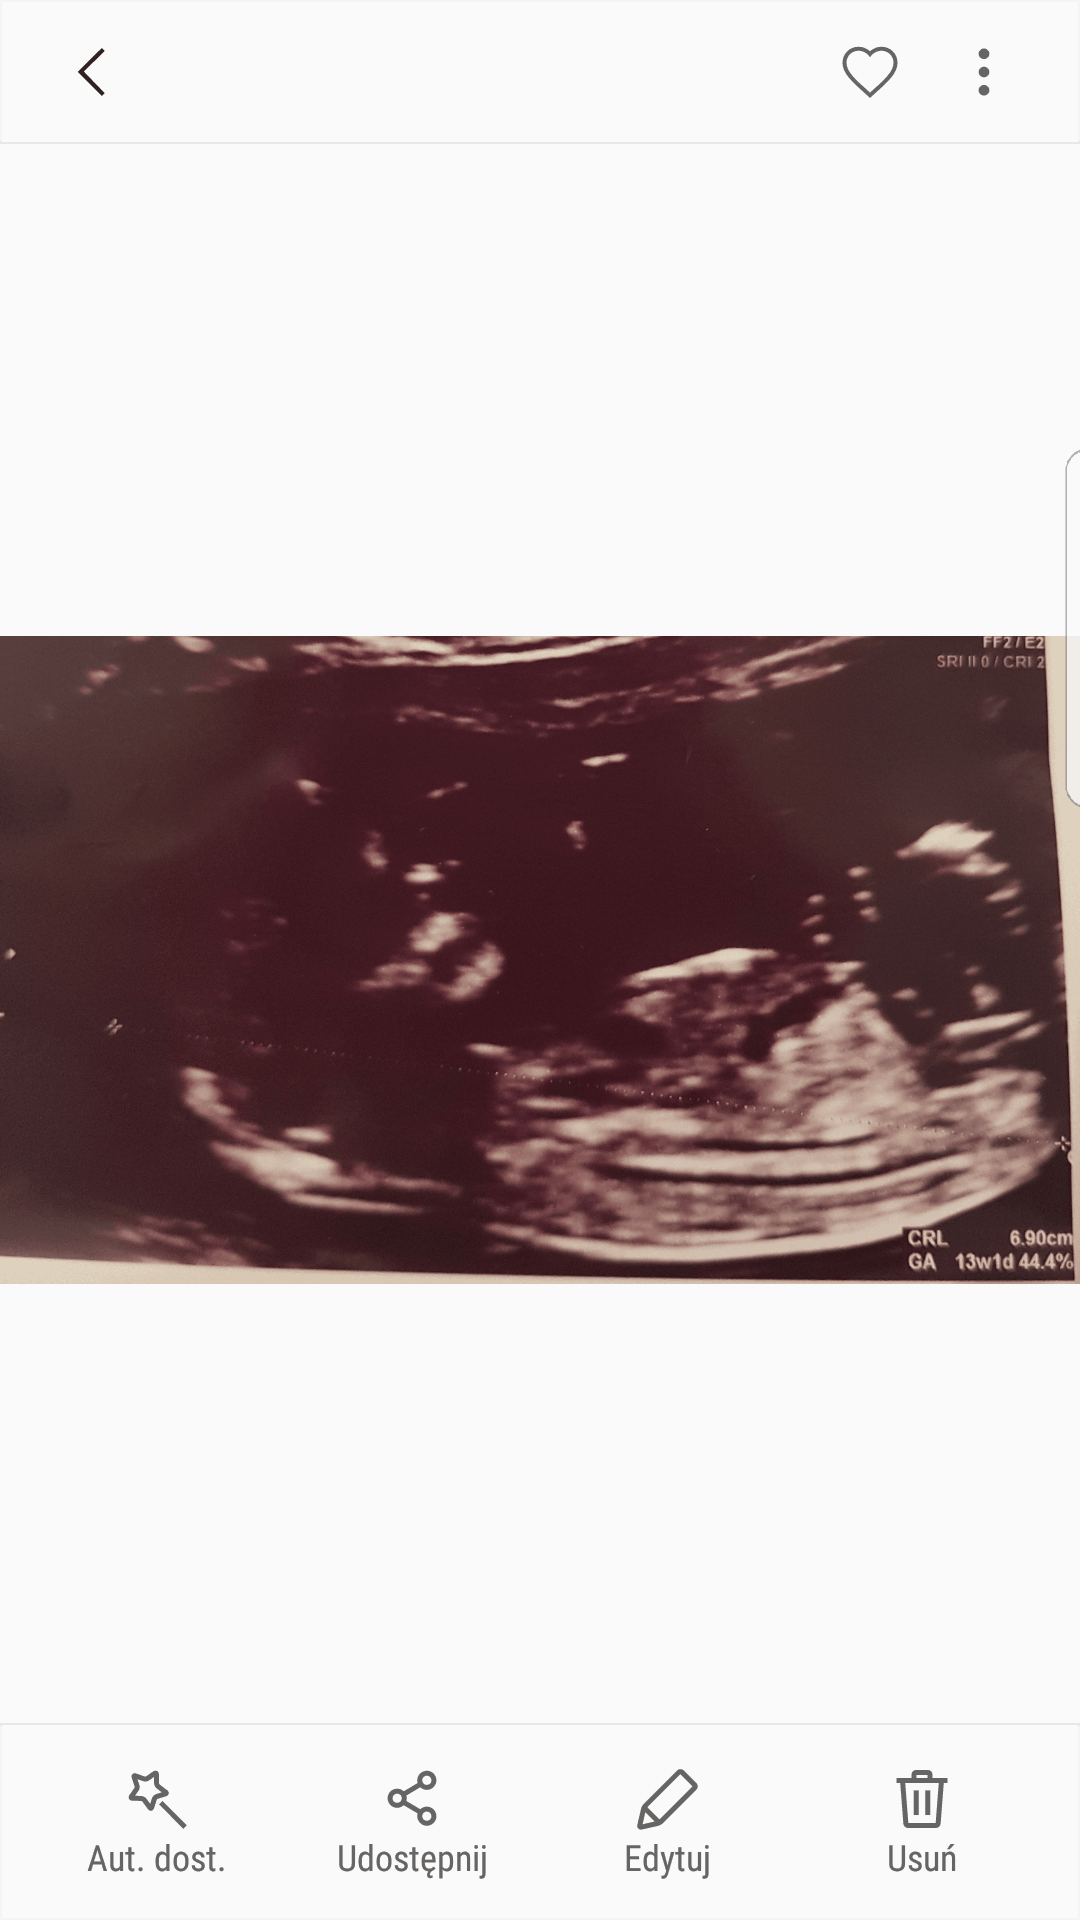

Chyba dziewczynka ale ciezko stwierdzic zdjecie troche ciemne...Cześć ciotki ❤Zobacz załącznik 839056

Troche ciemno w tych miejscach ktore chciałysmy oblukac :-)Cześć ciotki ❤Zobacz załącznik 839056

Link do: Chłopiec czy dziewczynka? - Blog mama ginekolog. Uniwersalna opowieść o życiu i wiedza medyczna dla kobietChyba dziewczynka ale ciezko stwierdzic zdjecie troche ciemne...

Mam jedno takie lepsze teraz się przypatrzylam ale jestem ślepaLink do: Chłopiec czy dziewczynka? - Blog mama ginekolog. Uniwersalna opowieść o życiu i wiedza medyczna dla kobiet

@zylwia tu masz objasnione co i jak, jak masz wiecej zdjec to moze uda Ci sie cos zobaczyc :-)